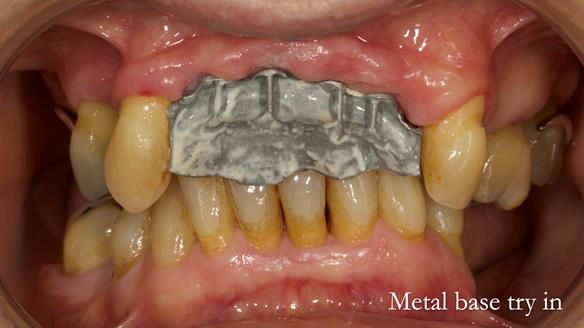

In this edition, I present the removable partial denture treatment for Jean, an 80-year-old woman with a sore mouth caused by a soft tissue-supported 'gum stripper' acrylic denture and a clenching habit. Below, I outline the step-by-step process of her treatment. It wasn't straightforward; I had to remake the denture after it fractured to achieve a satisfactory result. Each patient is unique, and sometimes a new RPD serves as a prototype. Occasionally, I need to make adjustments, learn from any mistakes, and refine the design to get it right.

The treatment has been a success over the past 4 years.